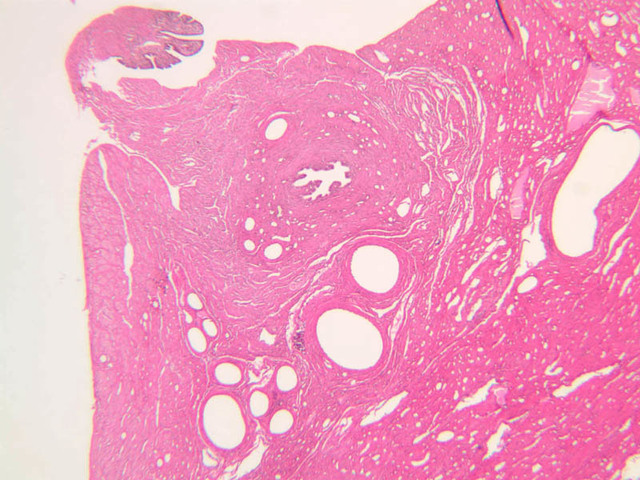

The uterus is a pear-shaped muscular organ, somewhat flattened from front to back. The expanded upper portion is referred to as the fundus, while its lower part, which protrudes into the vagina, is called the cervix. The lumen of the uterus is slit-like and is in communication with that of the uterine tubes (B-97, monkey uterus [1x, 1x, 1x, 1x]). The wall of the uterus consists of three layers: perimetrium, myometrium, and endometrium (B-97 [1x, 1x-labeled] [1x, 1x, 1x]; B-100 [1x, 1x]). The perimetrium is peritoneum which covers the uterus, but is lacking in the posterocaudal third below the peritoneal reflection (B-97 [2.5x, 10x, 20x, 40x]). The myometrium is the very thick middle layer consisting of bundles of smooth muscle cells arranged into several interwoven layers (slide B-93 [1x-labeled, 2.5x] [1x, 2.5x] [1x, 2.5x] [2.5x, 10x, 20x, 40x]). The endometrium is the innermost layer and is a glandular mucosa (B-97 [2.5x, 10x, 20x] [2.5x, 10x, 20x] [2.5x, 10x, 20x, 40x]). It consists of a surface epithelium which is invaginated into tubes called uterine glands. The glands penetrate into a very thick lamina propria referred to as the endometrial stroma. The surface epithelium is a mixture of ciliated and non-ciliated simple columnar cells, whereas the glandular epithelium consists mainly of non-ciliated secretory cells. The endometrial stroma has the appearance of a loose, rather cellular mesenchyme with numerous blood vessels.

The endometrium is subdivided into two main parts; the basalis and the functionalis (slide B-97). The basalis is deep, lying adjacent to the myometrium, it consists of stroma and the closed ends of the uterine glands and is not sloughed during menstruation. The functionalis is upper zone consisting of the remainder of the uterine glands with intervening stroma. It is lost during menstruation, but is replaced again with each menstrual cycle, by proliferation of the persisting elements in the basalis.

The menstrual cycle is a continuous series of events, dominated by the endocrine activity of the ovary, which repeats itself with a 28 day period. The endometrium participates by undergoing a series of structural changes which are roughly divided into three categories, the proliferative, secretory, and menstrual phases. These phases are listed below, examine each of the uterine slides and determine to which phase it belongs.